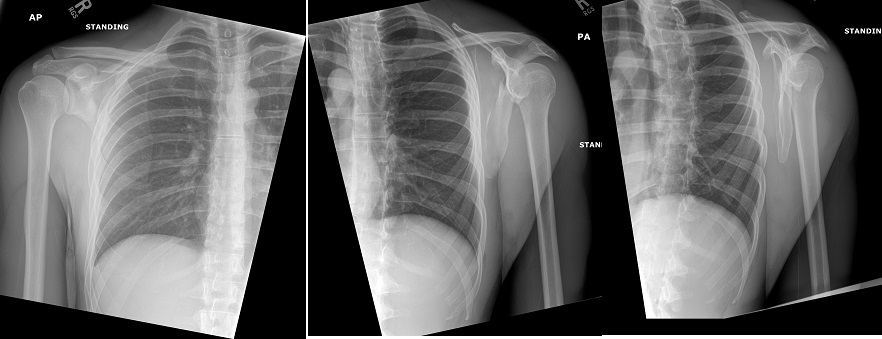

An 80 year old female presents to your office with a left ring finger deformity after a fall one week ago. She initially went to urgent care and xrays were unremarkable for a fracture (Figures 1 and 2). A photo of her left ring finger is shown in figure 3. On physical exam the left ring finger is in hyperextension at the PIP joint and flexion at the DIP joint. She able to flex her PIP joint with full motion. What is the best treatment option?